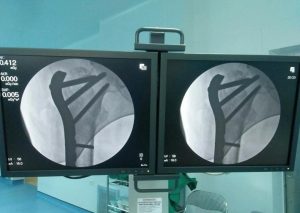

Bác sỹ vừa phẫu thuật, vừa xem hình ảnh xương trên màn hình C-ARM

bác sỹ vừa mổ, vừa xem thành quả của mình trên màn hình tăng sáng

Hình ảnh kết hợp xương gãy được xem online trên máy C-ARM của Nhật bản